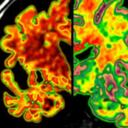

Apatía: signo de Alzhéimer

Un artículo publicado en la revista Alzheimer’s & Dementia señala que sentir apatía a los 40 años podría ser una señal de que la persona sufrirá más tarde la enfermedad de Alzheimer. Por apatía, entienden falta de interés o de motivación y una sensación diferente a la depresión.

Por eso, antes de catalogarlos como un problema de crisis de la mitad de la vida, se recomienda a las personas que sienten esta falta de energía para hacer las cosas, lo vean como una alarma de un potencial problema de memoria. A pesar de esto, los autores del trabajo no saben si primero aparece el alzhéimer o la apatía.